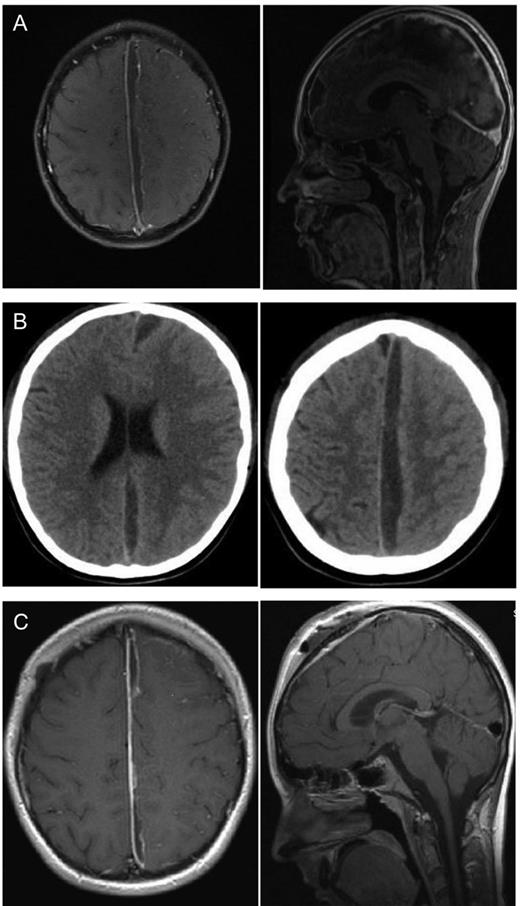

The first case is a 12-year-old boy who came to our department with a diagnosed sinusitis frontalis. Irrespective of the initiated antibiotic therapy, he developed a hemiparesis on the right side and worsening headache. An MRI scan of the brain (Fig. 1A) showed a parafalcine subdural empyema frontoparietal with a left side compression of the brain. The abscess was drained by a left parasagittal approach with neuronavigation. After draining the abscess the brain did not extend sufficiently, so we decided to put in a drainage for 2days to drain potential abscess material and to avoid a relapse of the subdural empyema. We expanded the antibiotic therapy from a single therapy to a triple therapy with amoxicillin, metronidazole and cefotaxim despite the absence of bacteria in growth culture. In spite of surgery and the antibiotic therapy, the patient's condition got worse with nausea, emesis and fever. An EEG showed pathological alterations and typical epileptical activity, convulsions were observed as well and a CT scan (Fig. 1B) 4days after surgery featured a progress of the abscess. Owing to the clinical aggravation and the increase of the abscess size, we decided to perform a second surgery. Intraoperatively, we found an encapsulated conglomerate of pus. We removed the capsule mostly and evacuated the viscous pus. Afterwards, we irrigated the abscess cavity with isotonic saline solution and put in a drainage. After second surgery the patient improved significantly. The antibiotic therapy was given for 3months under regularly control of infection parameters once a week and the symptomatic epilepsy was treated with levetiracetam. Subsequently, an MRI was performed at the day of discharge (Fig. 1C), which showed a regression of the abscess and another MRI 3months after the second surgery showed no further abscess. Until then the patient was seizure free.

Twelve-year-old boy with parafalcine subdural empyema. (A) Axial and saggital MRI section with administration of gadolinium. A parafalcine subdural empyema frontoparietal with left-side compression of the brain. It is seen a diffuse edema of the left hemisphere. (B) Axial native CT section. An enlargement of the empyema is visible 4days after first surgery with a diffuse edema of the left hemisphere without a significant midline shift. (C) Axial and sagittal MRI section with administration of gadolinium. Regression of the empyema is visible after the second surgery. A regressive edema of the left hemisphere is visible, especially the frontal abscess conglomerate is reduced.